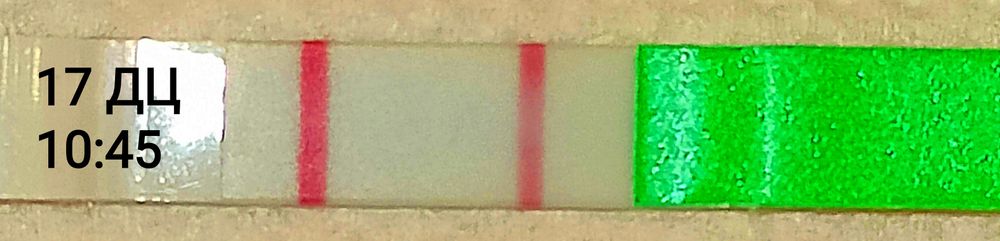

Екатерина, сегодня без сомнений супер положительный